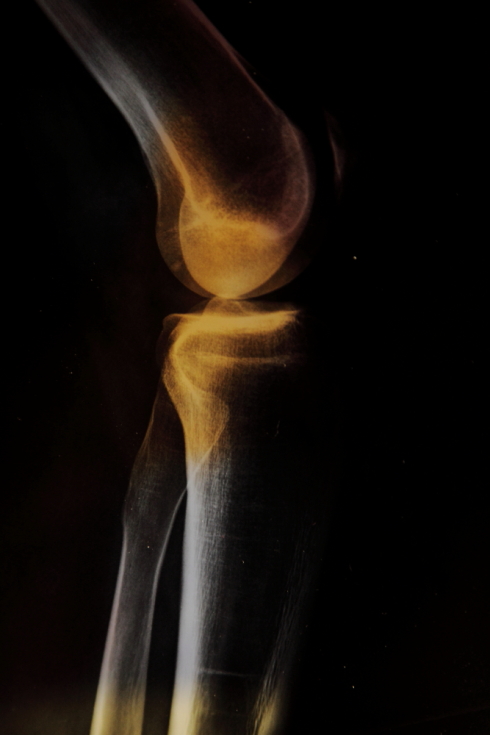

Photo works